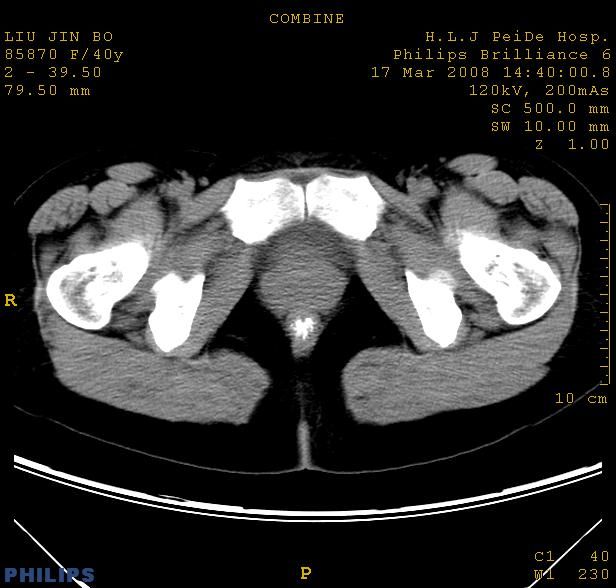

以下是引用qiuleiyu在2008-4-27 12:36:00的发言:[br]支持;右侧腰大肌后方神经源性肿瘤可能大,神经节细胞瘤?

以下是引用形影不离在2008-4-27 14:11:00的发言:[br]1.考虑右侧腰大肌脓肿。[br]2.左侧附件区炎症。[br]3.子宫增大,建议:进一步检查。